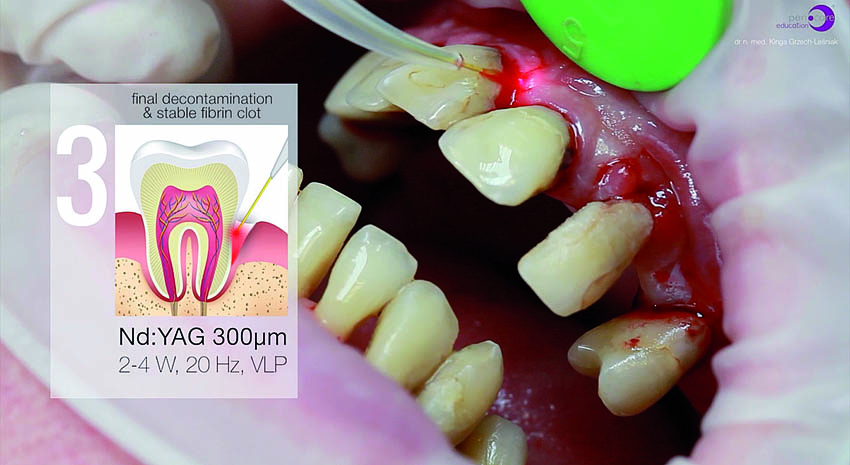

Για την τελική απολύμανση και αποστείρωση του πήγματος ινικής, εφαρμόστηκε και πάλι το laser Nd:YAG (Εικ. 13 και 14). Στην Εικ. 15 φαίνεται η κατάσταση αμέσως μετά τη χειρουργική με laser Er:YAG και την απολύμανση των περιοδοντικών θυλάκων με Nd:YAG